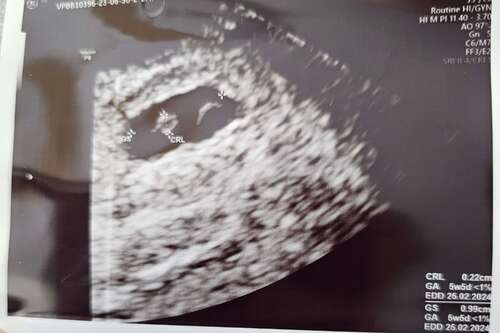

Ik ben in de ochtend na spoed geweest en daar hebben ze een echo gedaan, ( zie foto ) ze kon mijn niet zeggen of een foetus was of niet.. in de namiddag ook bloed laten trekken. 2 weken geleden was mijn hcg 3353 en progesteron 27. Vandaag was het 2390 en progesteron 9,... dat is dus geen goed teken